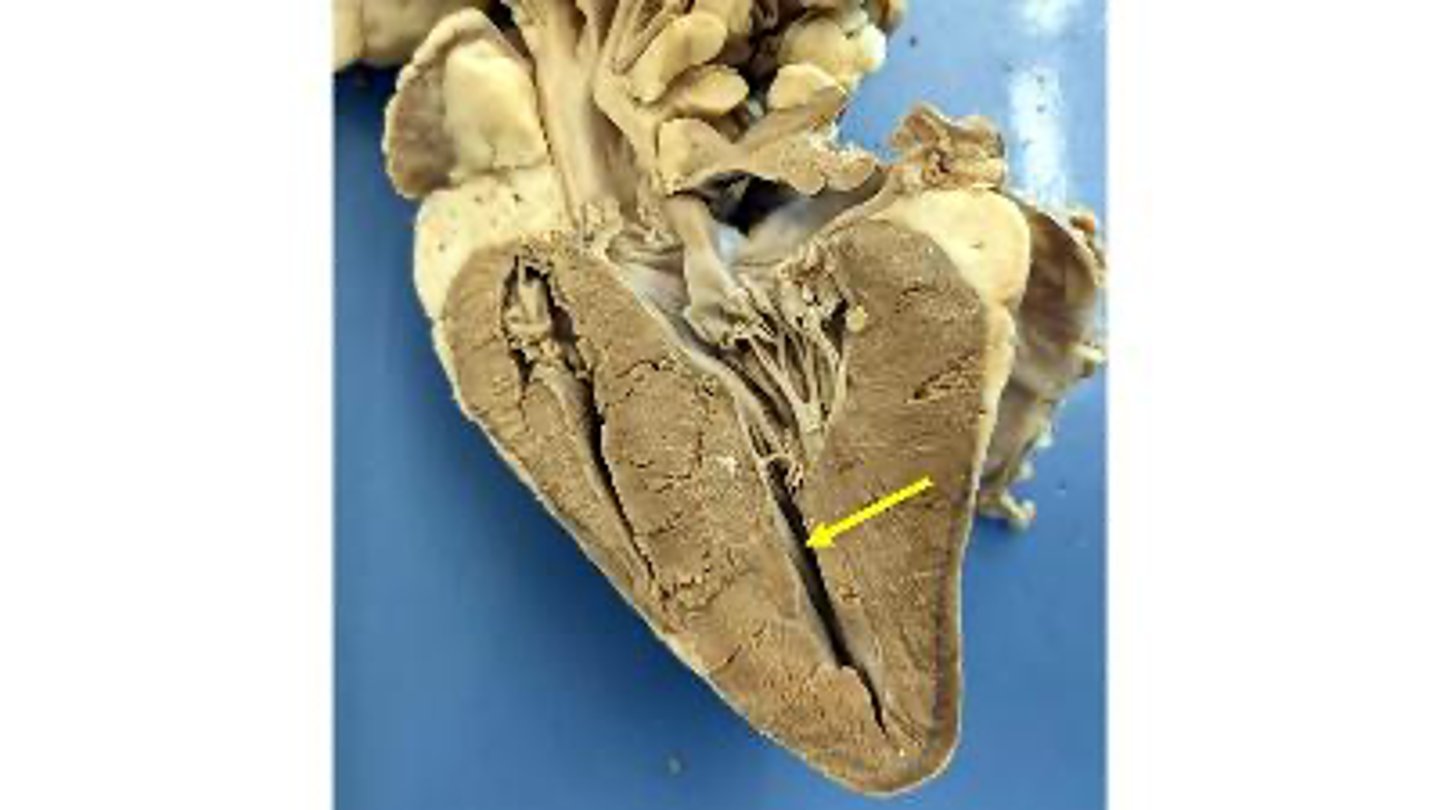

Left ventricle

what is this

Papillary muscle

Right ventricle

Interventricular septum